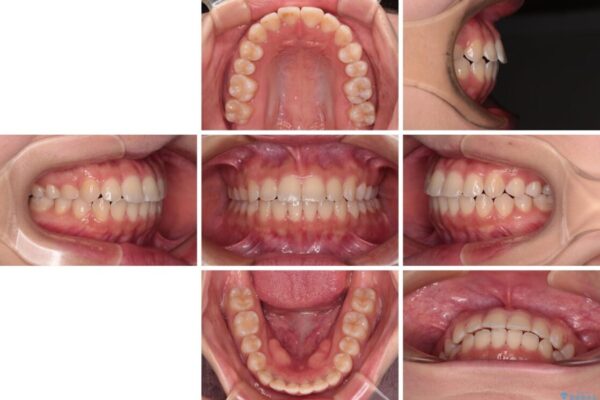

当初予定通り、1年で治療を終えることができました。

後戻り防止はマウスピースで行うため、急に自己管理が必要となるため、移動の最後をマウスピース矯正で行うことで、マウスピース非装着による後戻りリスクを回避する工夫をしています。

治療後

• 【モニター】短期間で終わりたい ワイヤー装置での非抜歯矯正 治療後画像